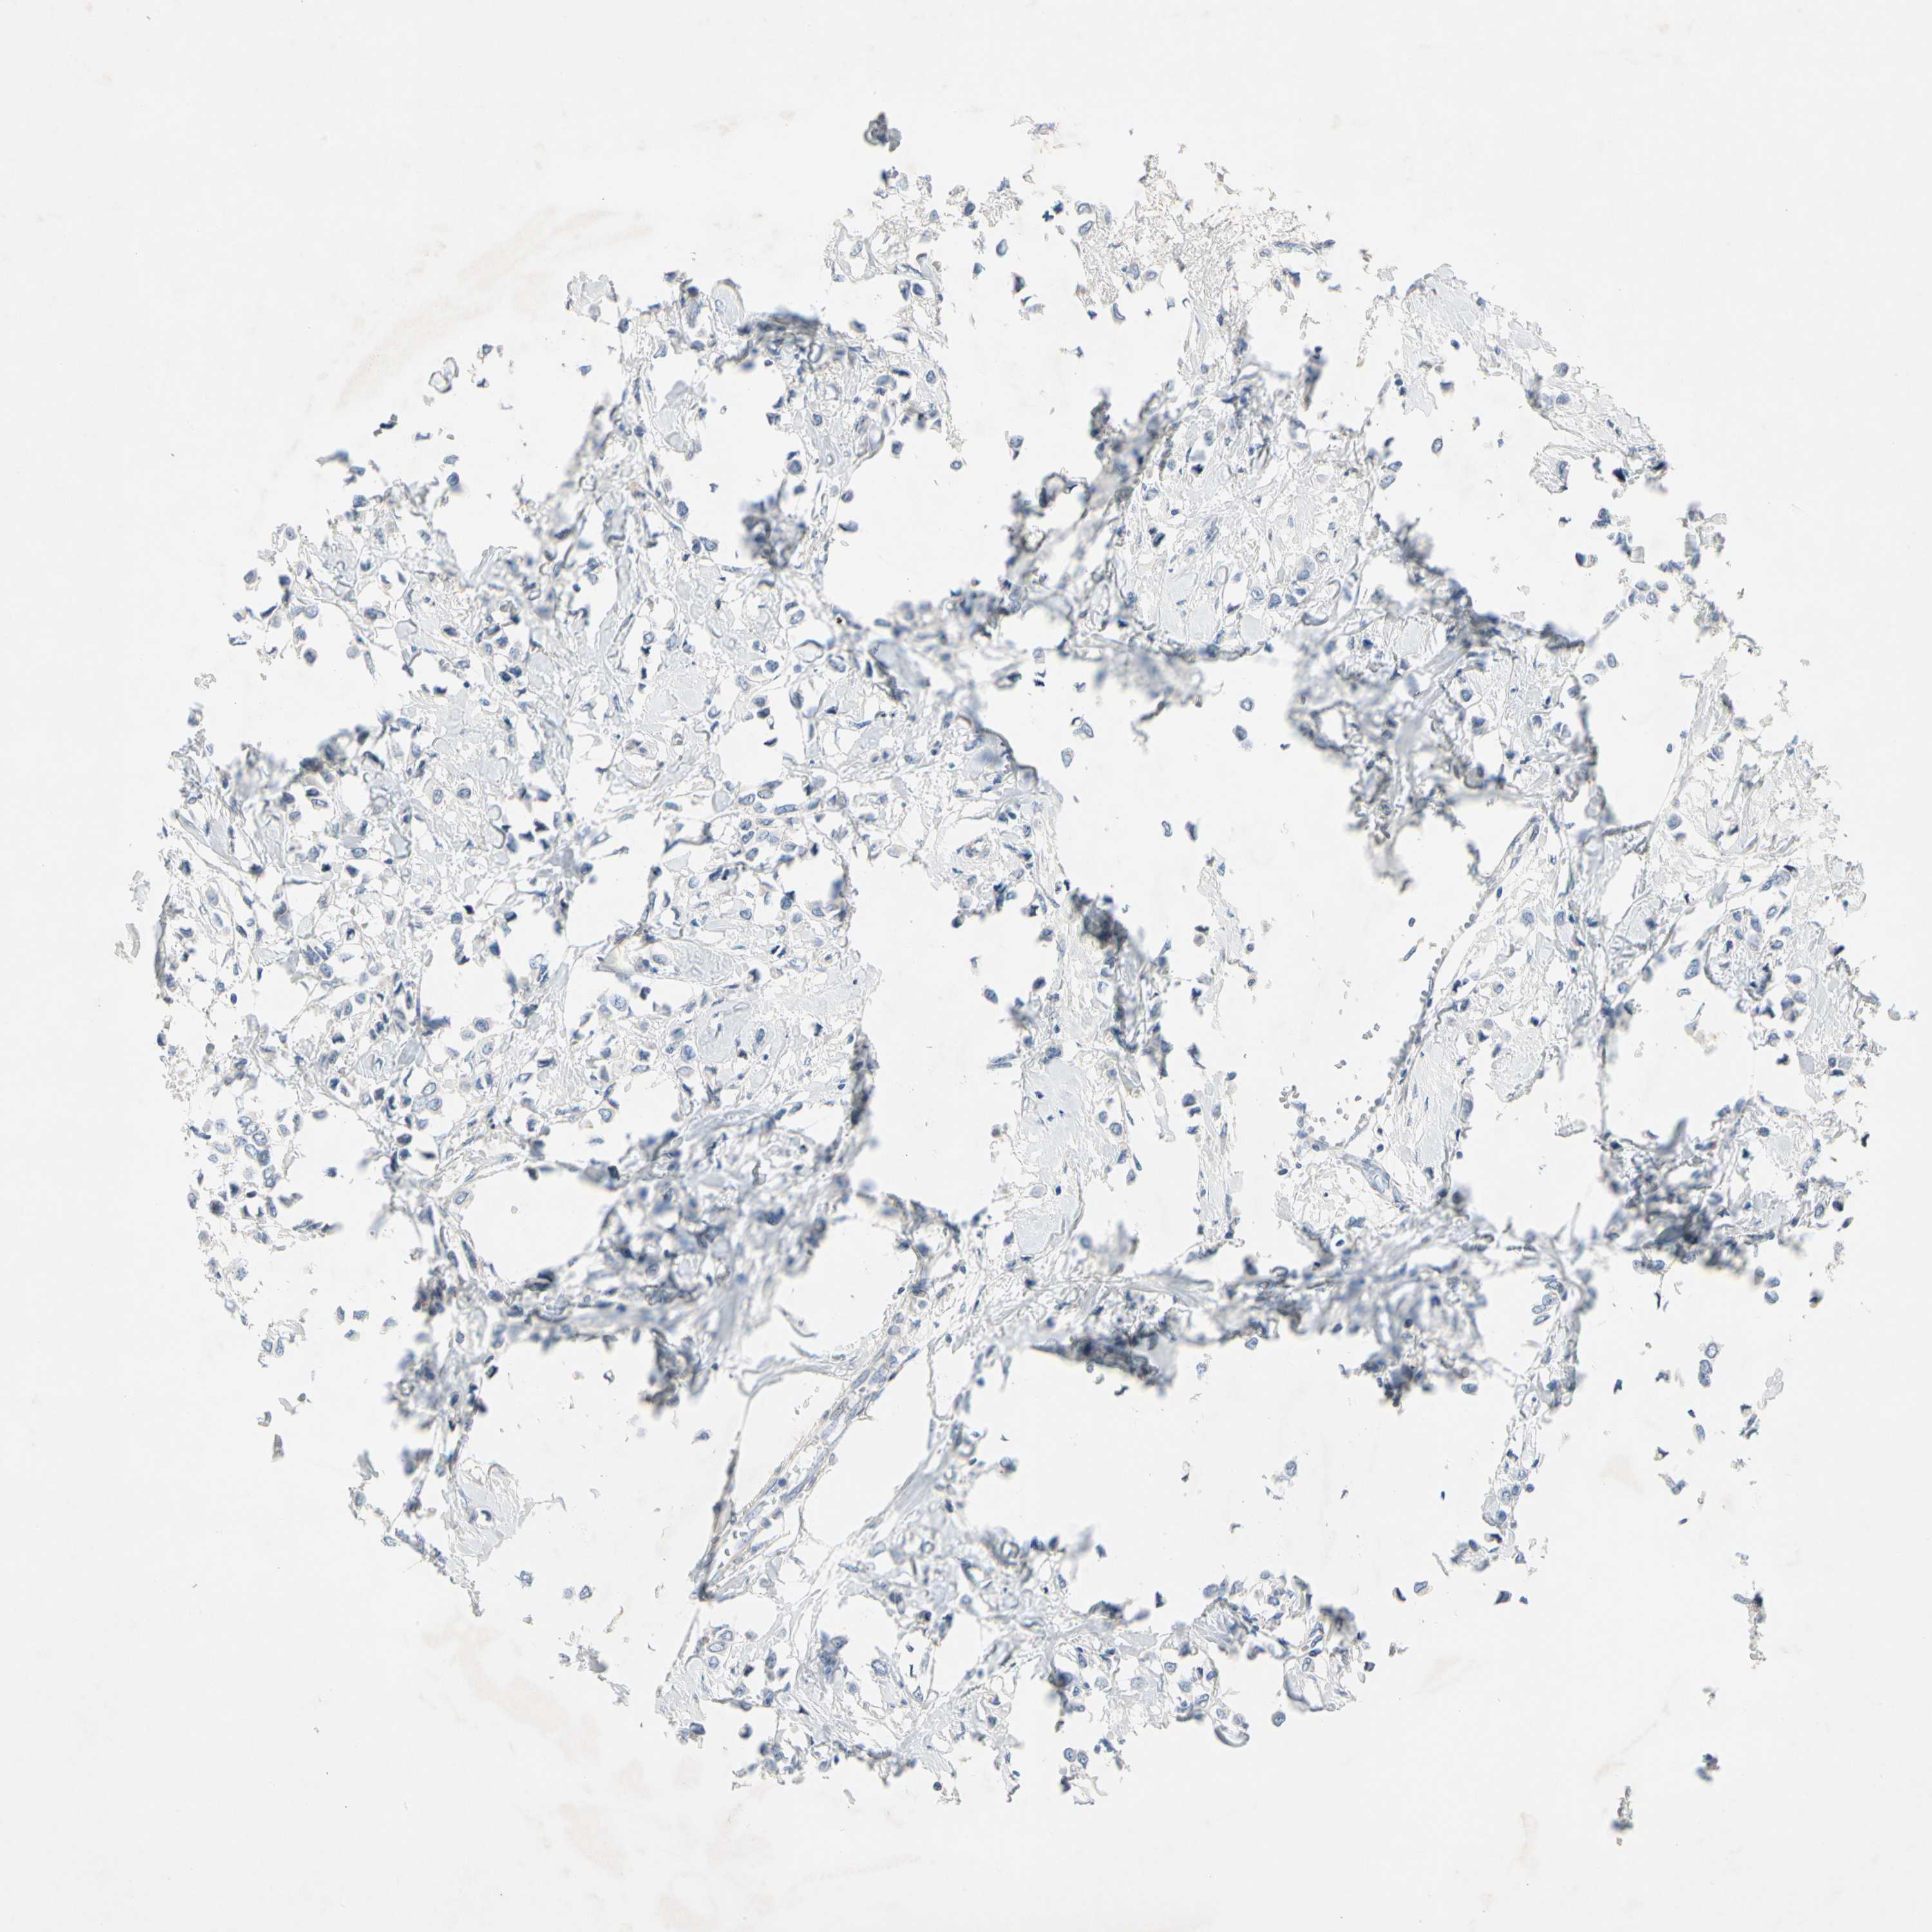

CANCER BREAST CANCER Show tissue menu

BRCA TCGA BRCA VALIDATION PROTEIN EXPRESSION

Breast cancer

Human cancer

Breast invasive carcinoma